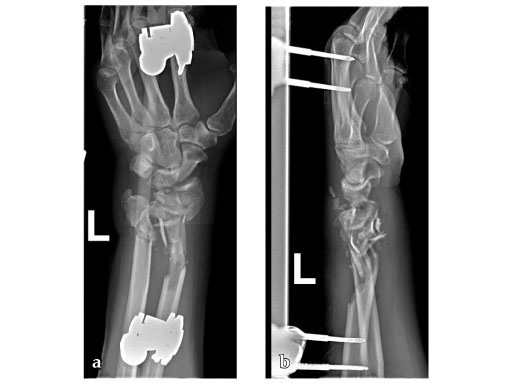

Fig 2ab: Eight months postoperative; full forearm rotation and 75% grip strength and wrist motion.

Fig 3ab: Full motion recovery.

Case provided by Jesse Jupiter, Boston